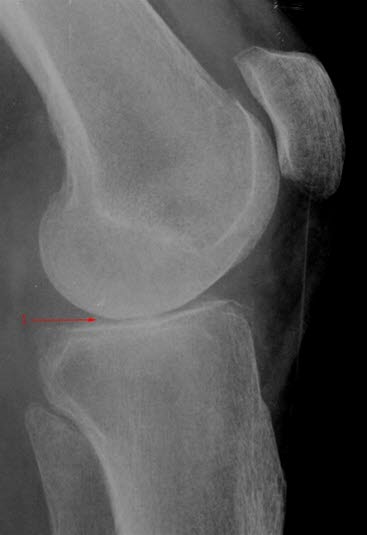

Gonartrose, moderat, side

Lett redusert bruskhøyde i kneleddet (1).